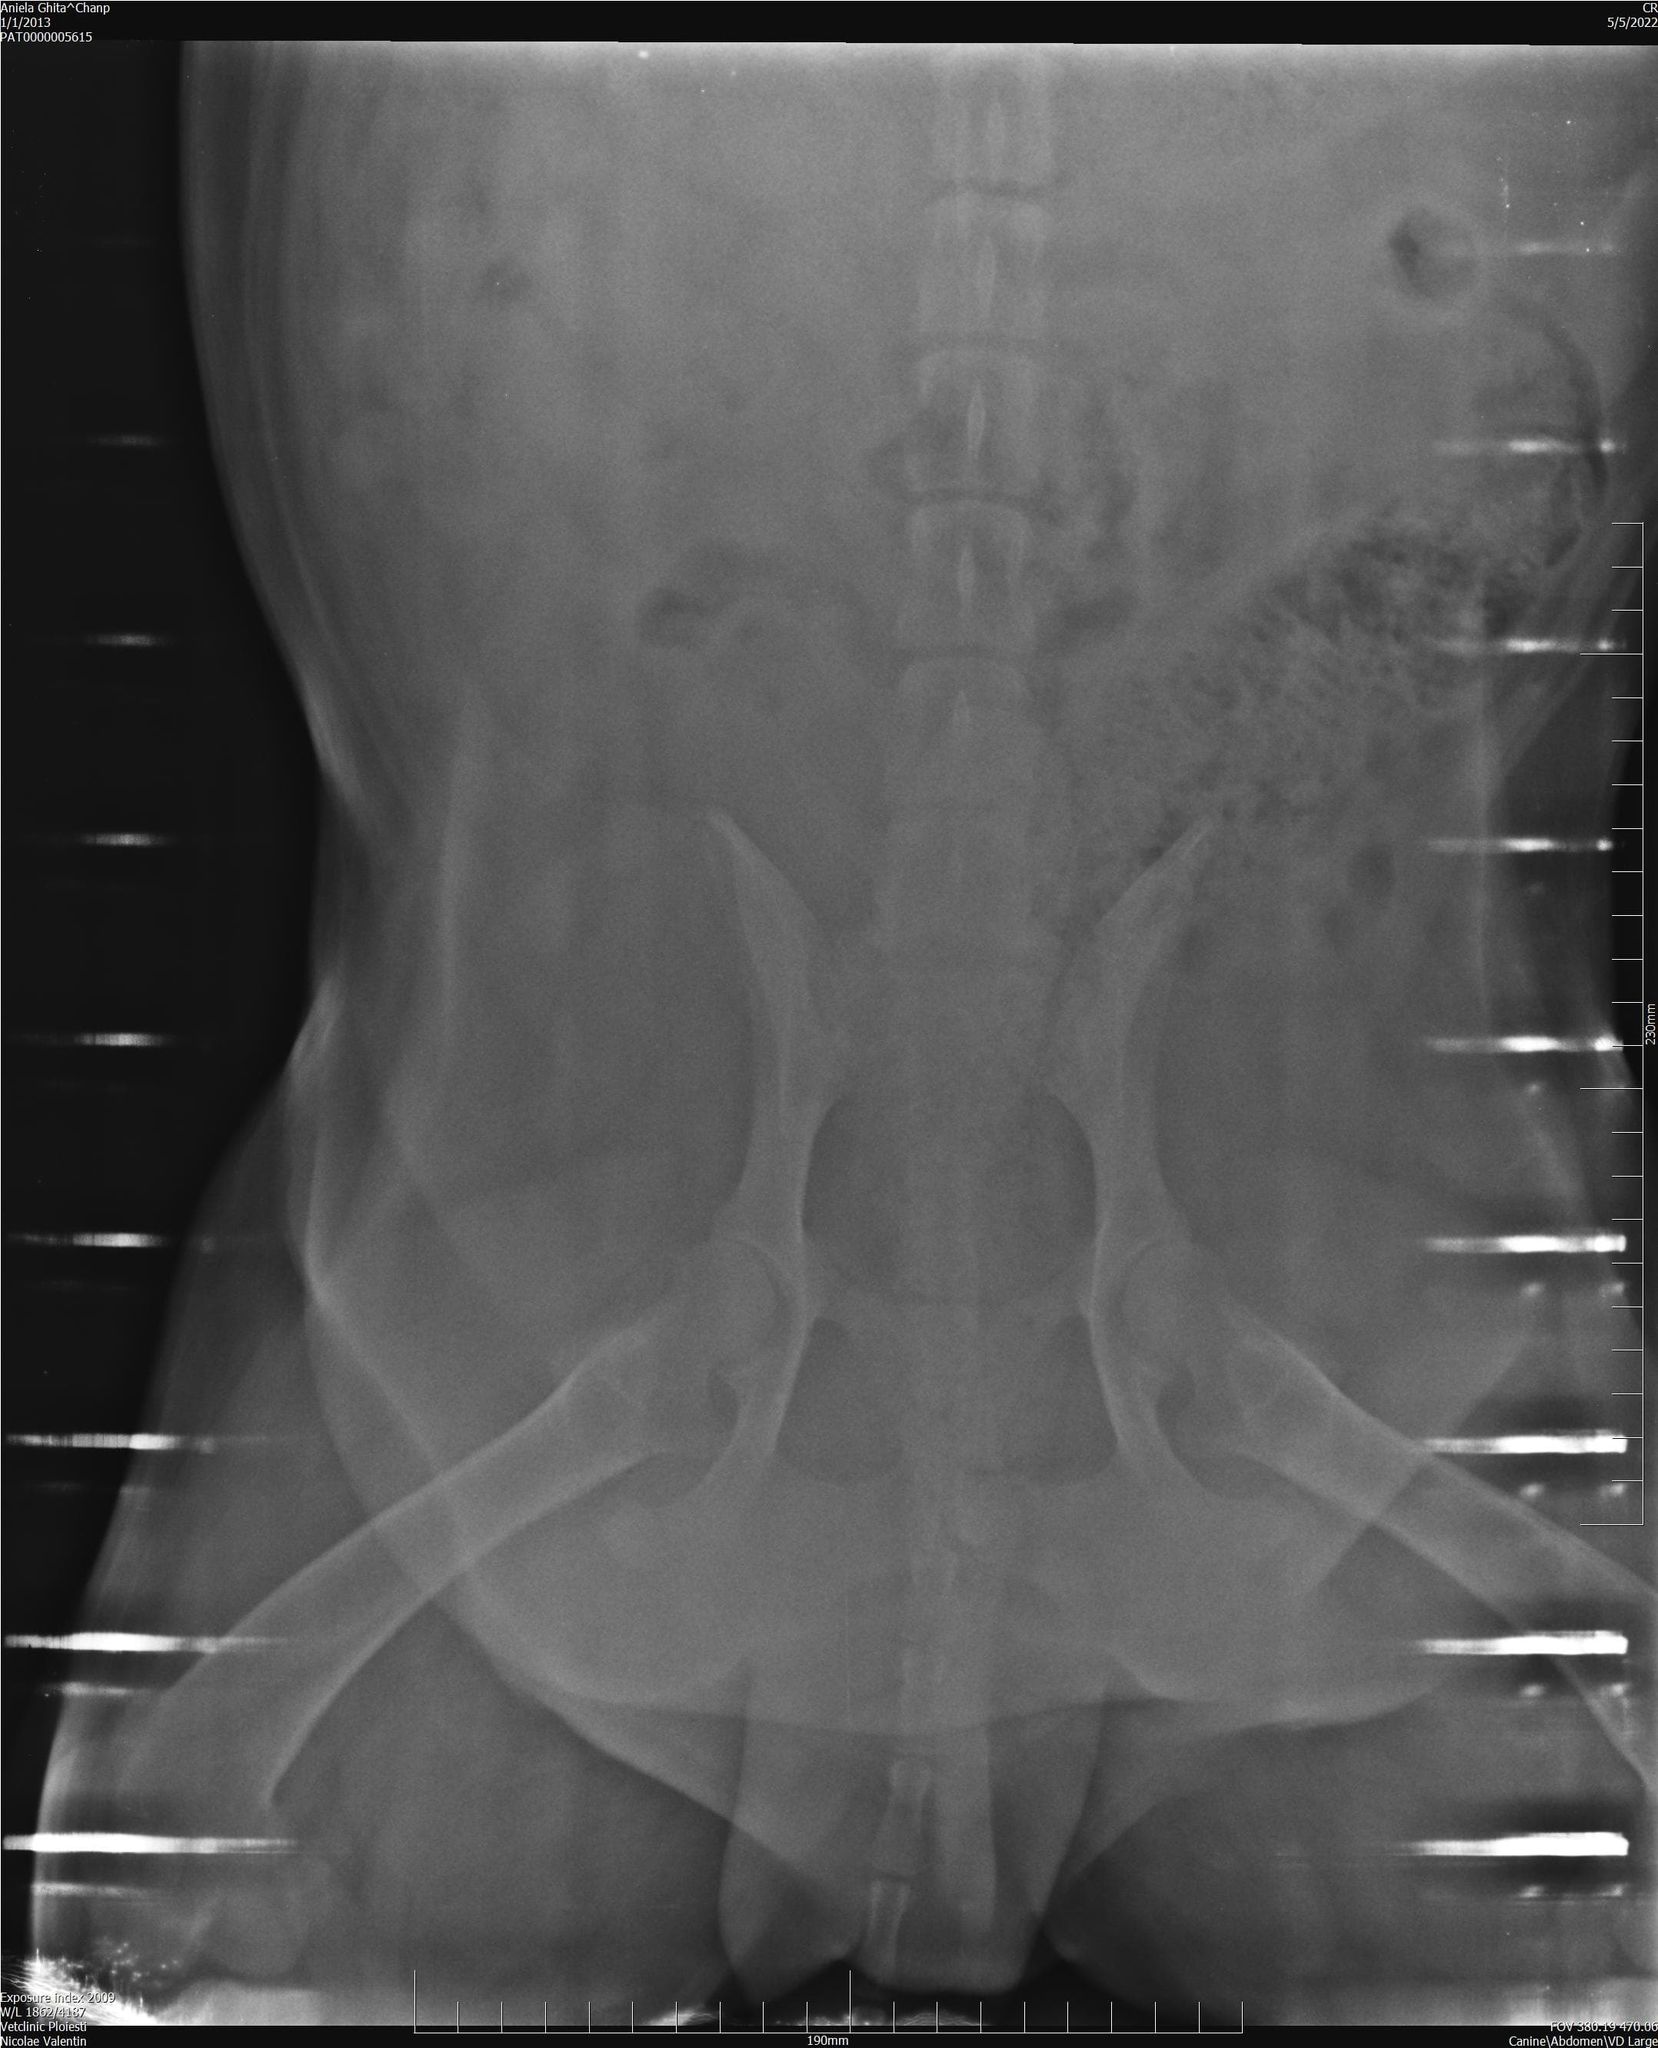

Befund Mai 2022: Degenerative Osteoarthritis der Femur-Tibia-Patella- und Hüftpfanne

| zur Besonderheit: | Degenerative Osteoarthritis der Femur-Tibia-Patella- und Hüftpfanne, schwere Beinfehlstellung hinten beidseitig, seit mind. September 2019 im Tierheim |

| zur Besonderheit: | Degenerative Osteoarthritis der Femur-Tibia-Patella- und Hüftpfanne, schwere Beinfehlstellung hinten beidseitig, seit mind. September 2019 im Tierheim |